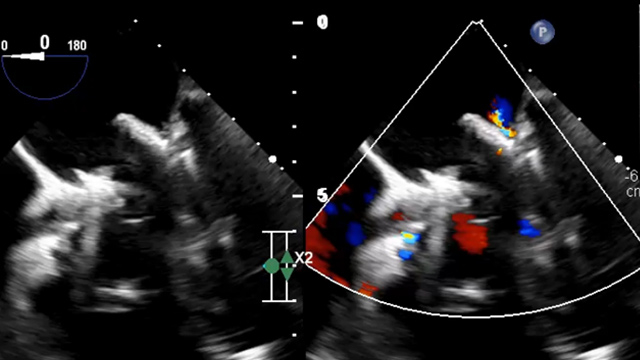

Right heart catheterisation and CT scan for the assessment of A-V valve treated percutaneously

21 May 2025 – From EuroPCR 2025

This session evaluates right heart catheterisation and cardiac CT imaging in the assessment of percutaneously treated atrioventricular valves. Explore clinical outcomes, invasive physiology characterization, annular remodeling, and pulmonary hypertension impact on mitral and tricuspid valve interventions.